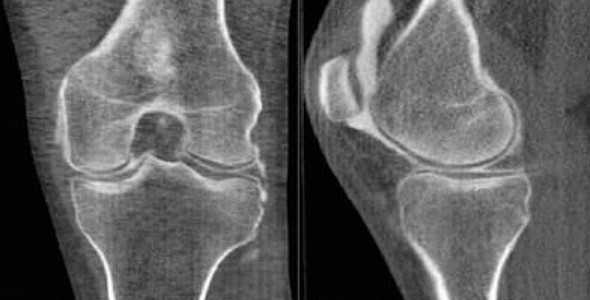

КТ колена

С помощью компьютерной томографии визуализируют нарушения связочного аппарата, костных суставных поверхностей, гиалинового хряща, синовиальной оболочки и капсулы сочленения. Ограничение подвижности и боль возникают чаще при травмах, воспалительных и дегенеративных патологиях.

КТ коленного сустава позволяет диагностировать хондромаляции (разрушение хряща), повреждения менисков, разрывы крестообразных связок. В результате контрастной процедуры выявляют онкологические процессы, заболевания сосудов, липоартрит и пр.